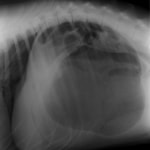

術前レントゲン

腹部臓器が胸腔内に脱出し、腹部と胸部の境界および心臓や肺の陰影が不明瞭になっています。また、胸腔内に消化管のガス陰影が認められます。